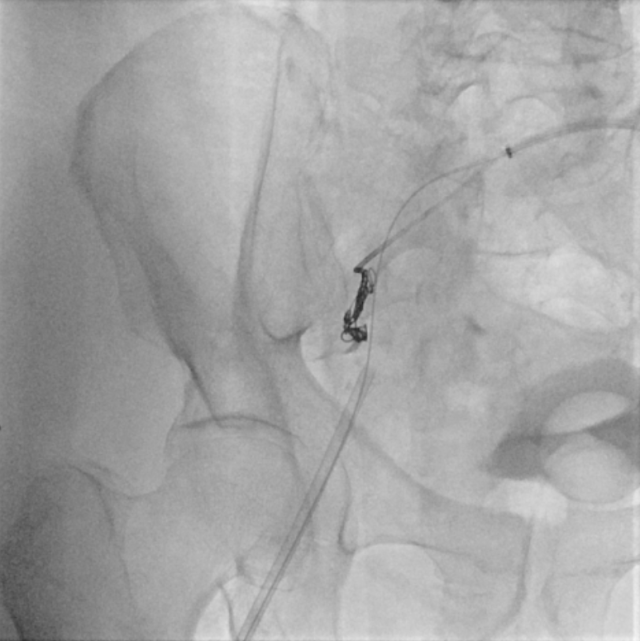

医生利用 “翻山(Cross-over)” 技术,从左侧绕道攻克右侧,先向髂内动脉瘤的分支血管精准投放金属弹簧圈。这些精细的小圈在瘤体内迅速缠绕,形成一道物理 “封印” 屏障,初步阻断分支血管的血流倒灌。

右侧髂内动脉瘤分支血管弹簧圈栓塞图